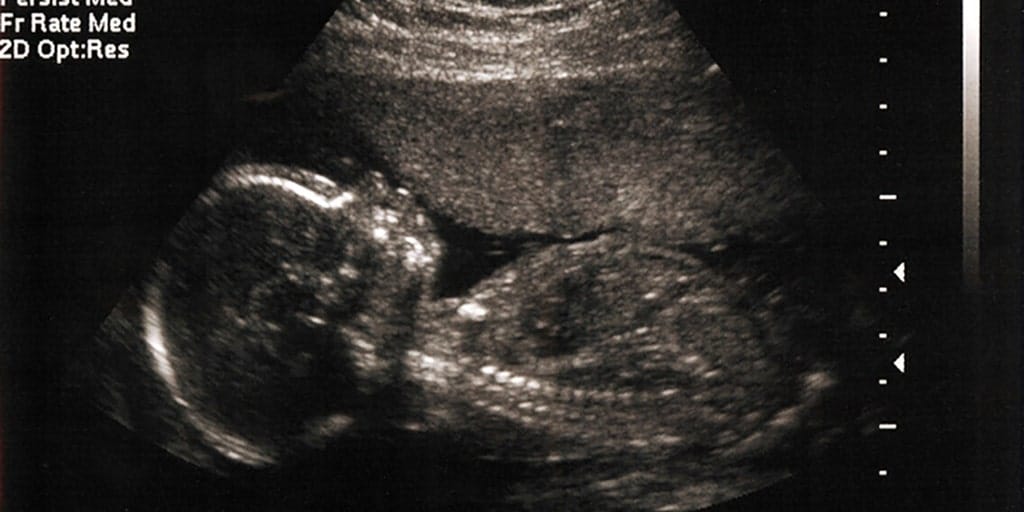

Pregnant?

Pregnant? Need help?